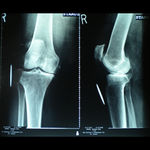

A 62 year old, female patient presented with a history of increasing right knee pain and loss of function over a 3-year period.

On clinical and radiological examination, she was assessed as having Medial Compartment Osteoarthritis. A uni-compartmental knee replacement was recommended and performed in June 2011. Patient has gone onto complete recovery with a satisfactory clinical outcome. She returned to independent function, six weeks after the surgery and now has a pain-free existence with full function in the right knee.